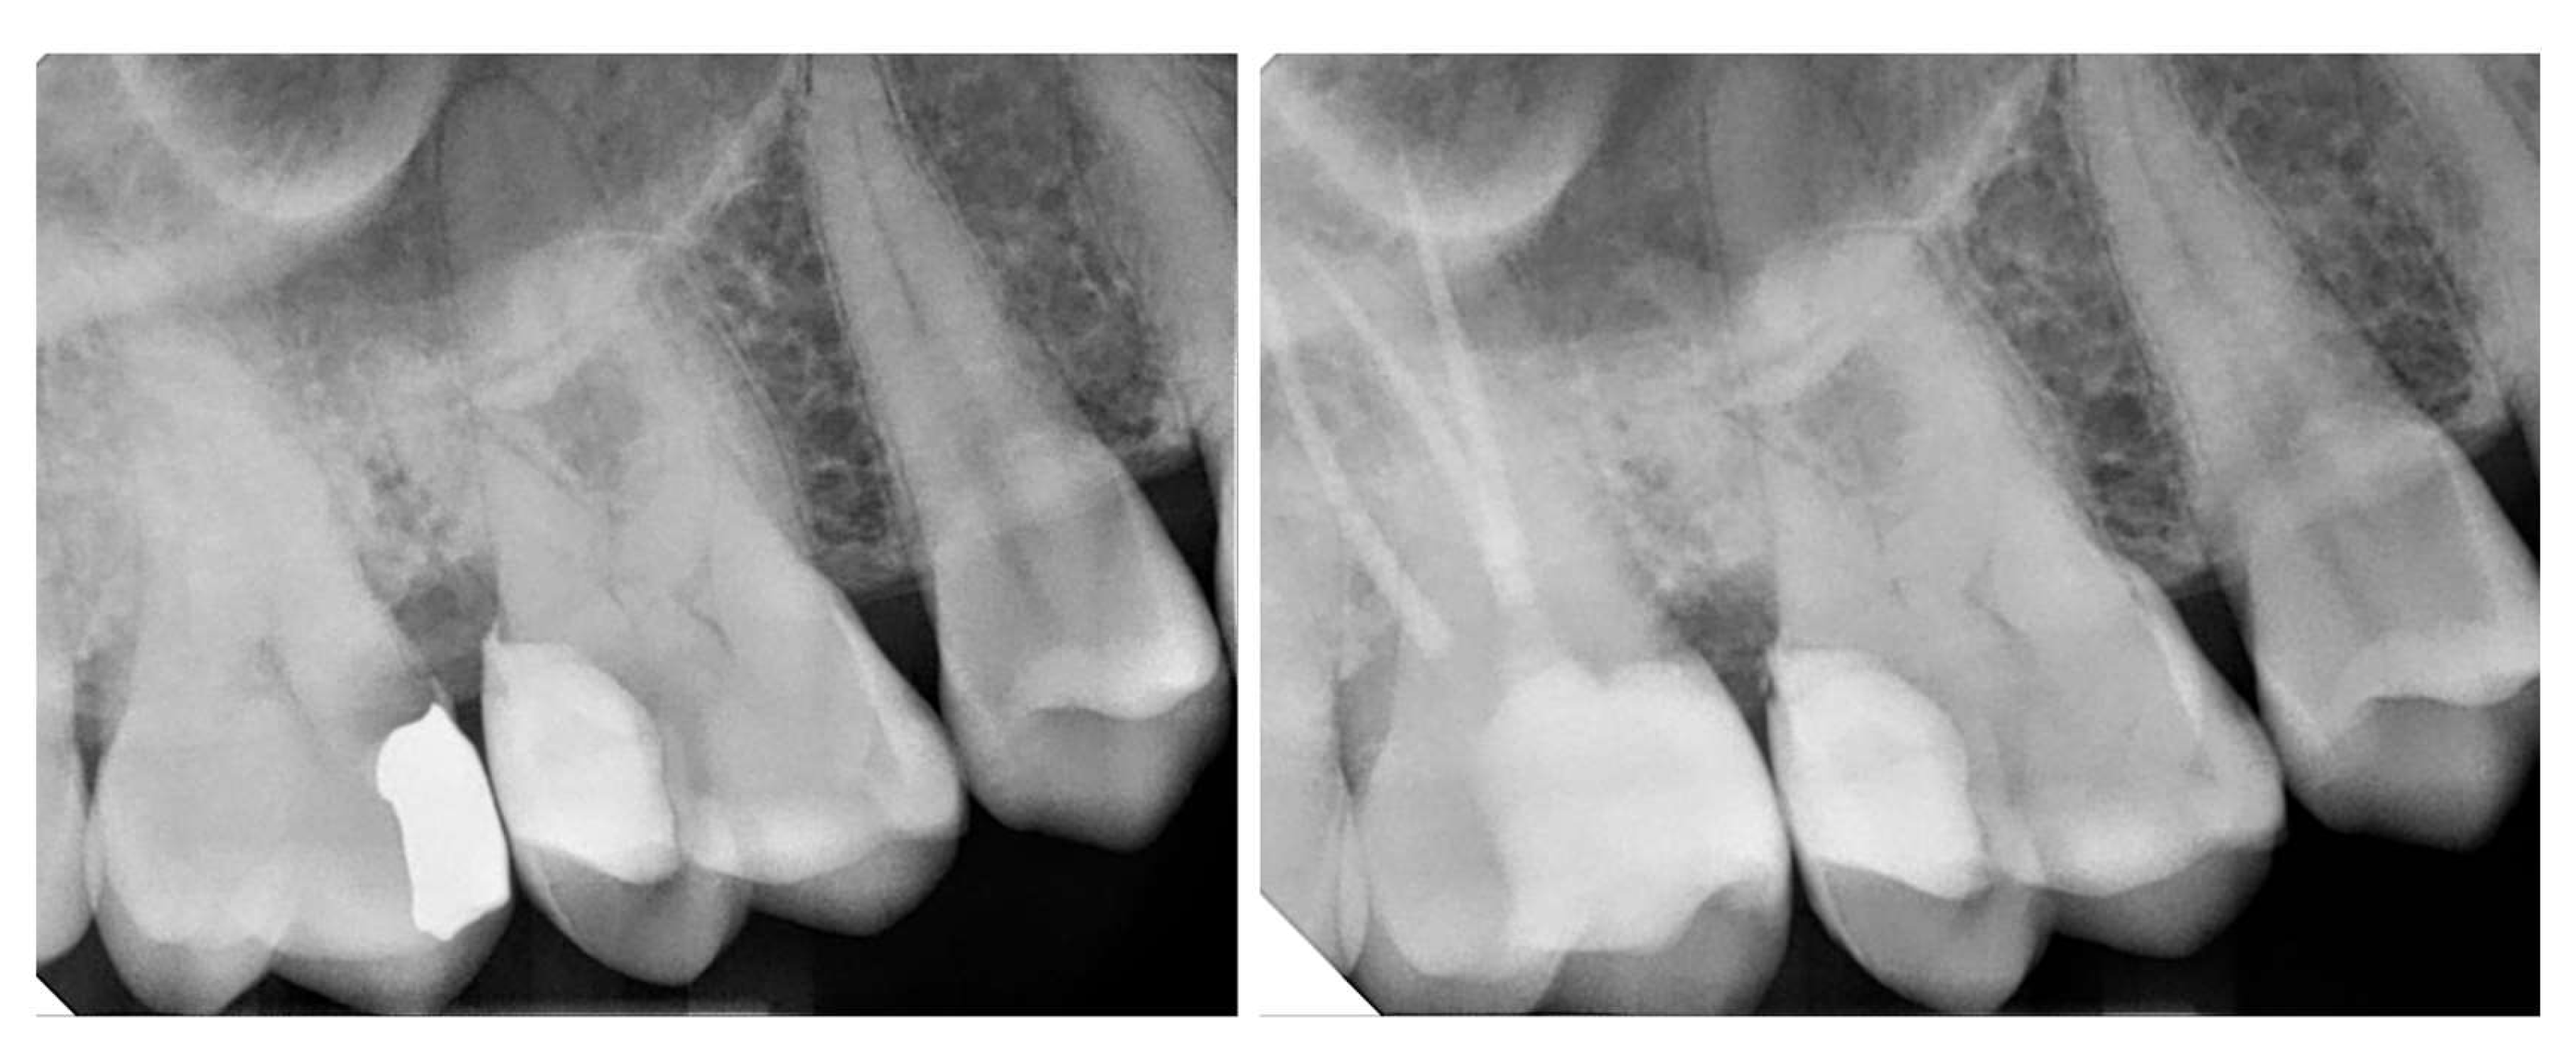

3.4. Microleakage & Marginal Adaptation

| Sadeghnezhad et al [1], 2024 | Meta-analysis | N/A | Data analysis was done by biostat software, 7 studies were included. | The use of DME had a positive effect in reducing microleakage compared to indirect restorations with subgingival extension. |

| Zhang et al [38], 2021 | In vitro study | Total etch | Specimens were coated with two layers of nail varnish extending 1 mm beyond the crown margins and immersed in a 0.55% methylene blue solution. Gingival microleakage was then evaluated under a stereomicroscope. | In endodontically treated teeth restored with an endocrown extending into the pulpal chamber, DME increased fracture resistance but did not reduce microleakage levels. |